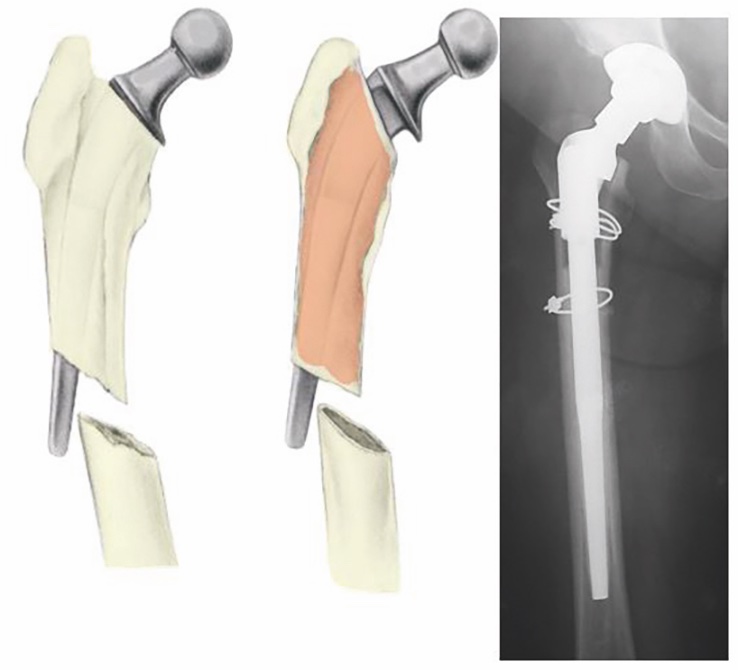

Nelle fratture tipo B2 con stelo instabile e B3 con stelo instabile e perdita di sostanza ossea il trattamento consiste nella rimozione della componente femorale e nell’impianto di uno stelo da revisione (Fig. 9).

Attualmente è preferibile utilizzare steli lunghi non cementati modulari in quanto consentono di realizzare una sintesi endomidollare che favorisce la consolidazione della frattura e di ripristinare la biomeccanica articolare tramite la modularità della porzione prossimale. Nei casi in cui la frattura si realizza sotto l’istmo femorale è possibile utilizzare steli lunghi non cementati che prevedono una stabilizzazione con viti trasversali distali.

Nel gruppo tipo B3 la perdita del tessuto osseo prossimale pone talvolta dei problemi per la fissazione dello stelo. Nei pazienti più giovani per riempire i difetti ossei è possibile utilizzare innesti ossei sotto forma di osso truciolato o di stecche ossee e, nei casi più gravi, interi segmenti omologhi di femore prossimale 36.

L’impiego di stecche di osso di banca permette di ottenere una migliore stabilità meccanica, di ottenere un ripristino del bone stock e di favorire il processo di consolidazione della frattura 3, 4, 37. Il trattamento mediante stecche corticali richiede la disponibilità di una banca dell’osso e un’ampia dissezione dei tessuti molli per poter posizionare e stabilizzare la stecca corticale. Chandler et al. 38 hanno analizzato una casistica di 19 pazienti trattati con stecca corticale fissata mediante cerchiaggi riportando in 16 casi un eccellente risultato con consolidazione a 4,5 mesi. Emerson et al. 39 riportano una percentuale di consolidazione pari al 96,6% a un tempo medio di 8,4 mesi.